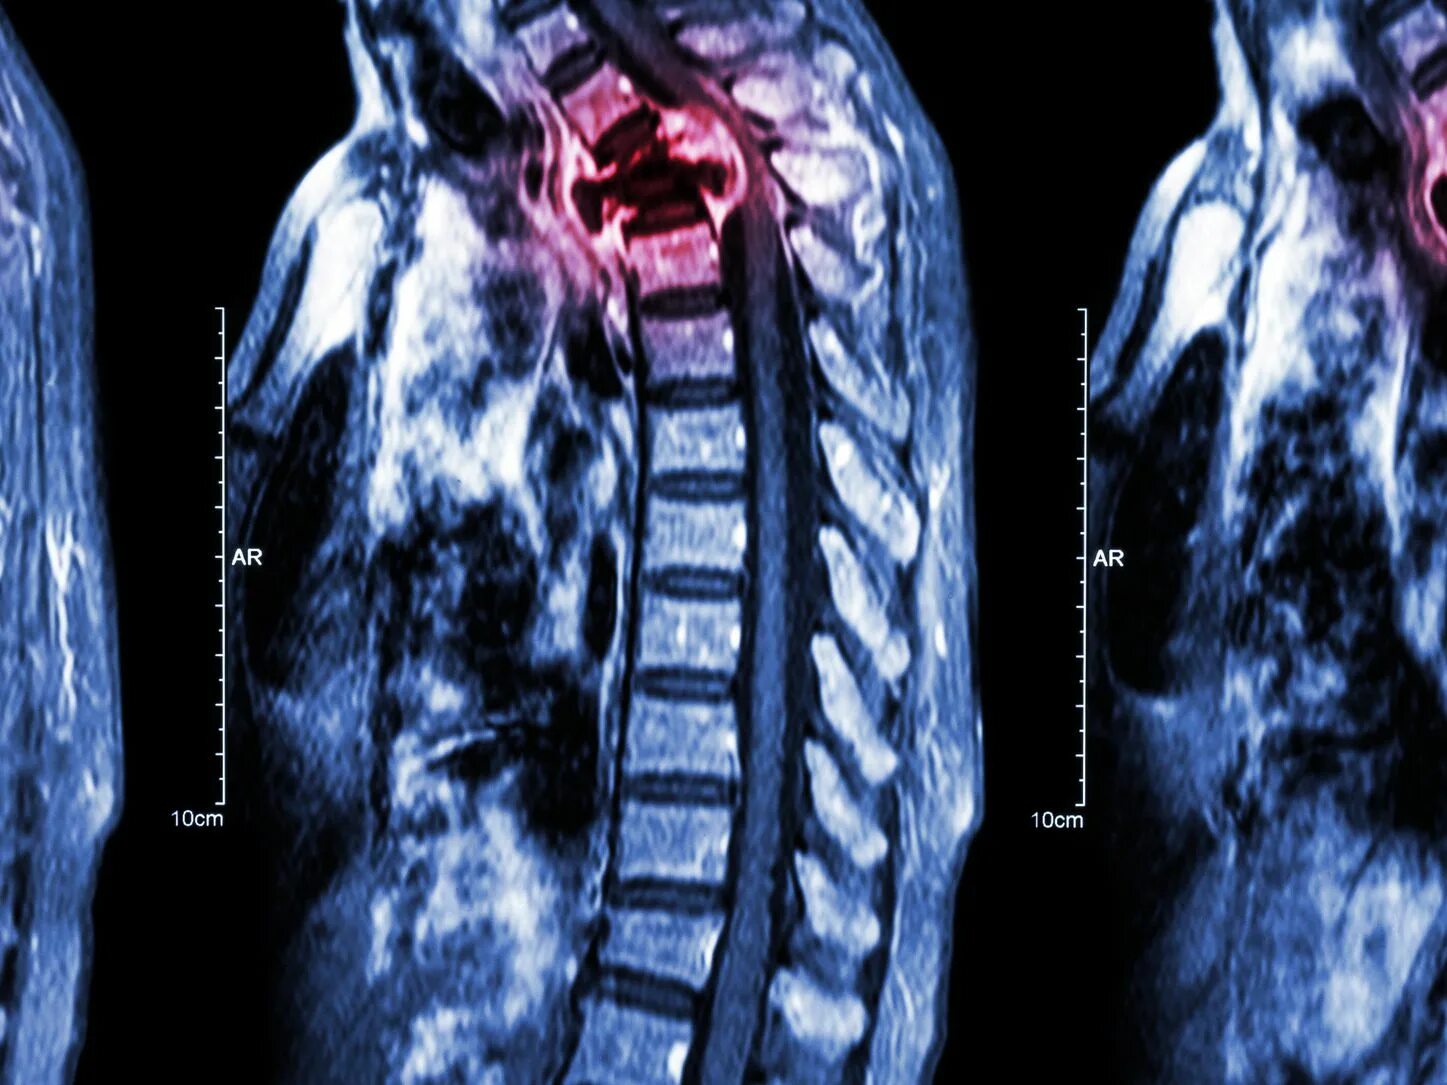

Как быстро растут метастазы